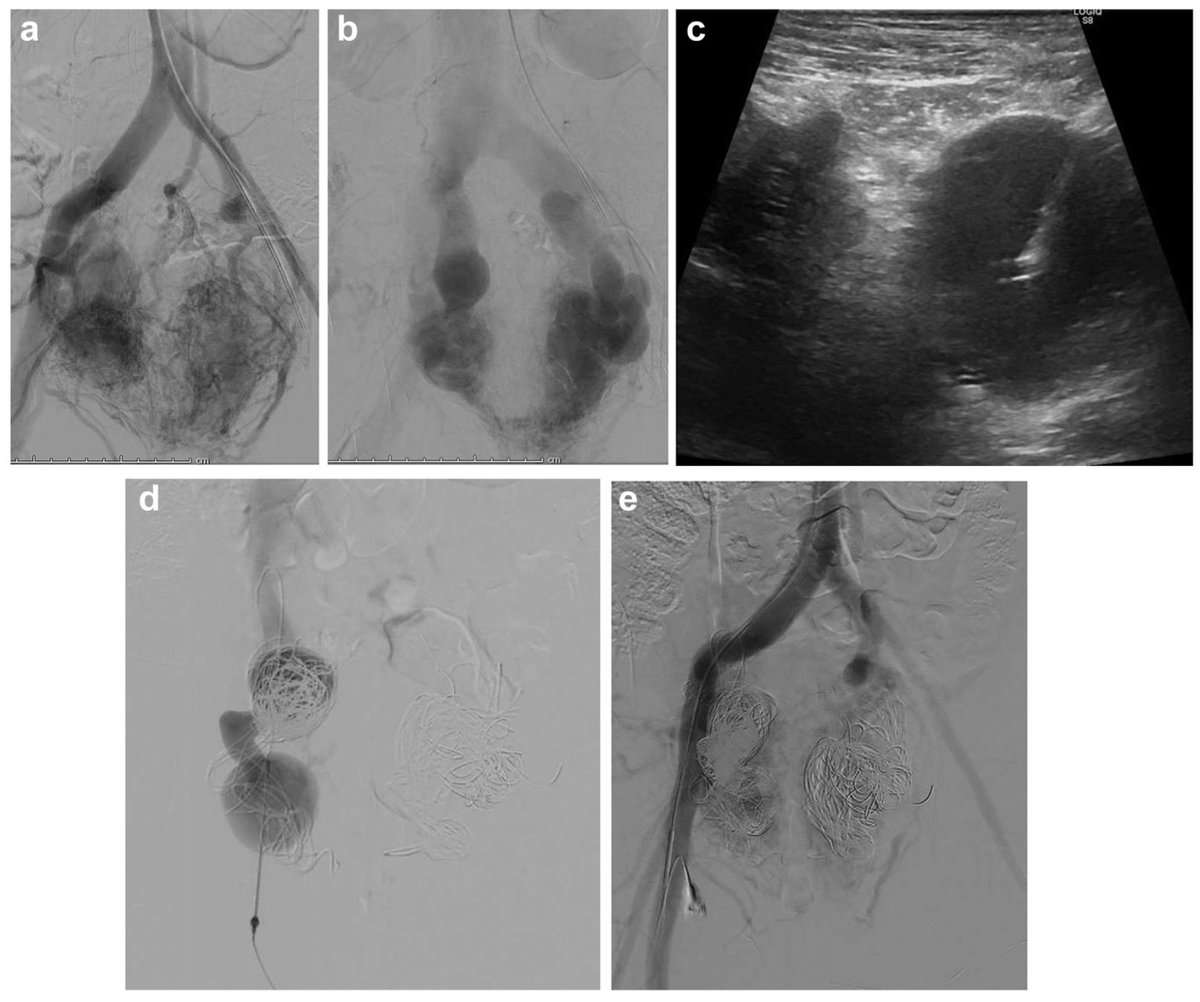

Better visualization, smarter planning. In this JVS-VL pilot study, CEUS + UHFUS showed promise for improving preop mapping and streamlining LVA in patients with lymphedema.